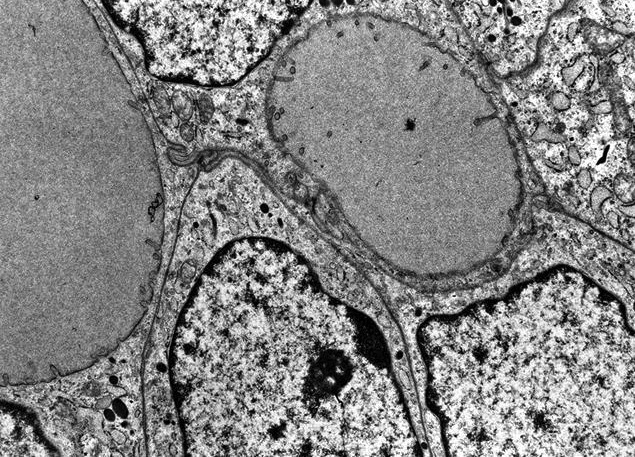

Electron microscopy description

- Similar to normal thyroid gland and hyperplastic nodules

- Hyperfunctioning follicular adenomas: organelle rich cytoplasm, especially rough endoplasmic reticulum; numerous, long microvilli on surface (Am J Clin Pathol 1982;78:299)

- Clear cell follicular adenomas: cytoplasmic vesicles of variable size; these may be dilated cisternae of the rough endoplasmic reticulum or mitochondria, lysosomes or endocytic vesicles (Virchows Arch A Pathol Anat Histol 1978;380:205)

Electron microscopy images